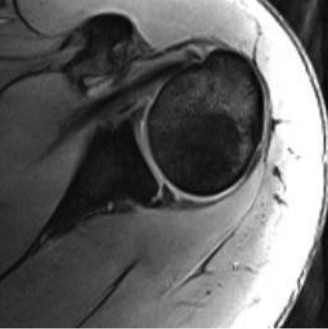

The correct answer is (B). An MRI showing a rotator cuff tear is considered diagnostic of a rotator cuff tear because of its high sensitivity, specificity, and accuracy. It has superb soft tissue imaging abilities (see Fig. 2–5). However, it should be noted that while MRI usually can differentiate between partial- and full-thickness rotator cuff tears, this varies with the power and accuracy of the MRI facility. This is also true with the ability of MRI to differentiate between partial-thickness rotator cuff tears and subacromial bursitis. An arthroscopy is needed for definitive differentiation of these pathologies.

Figure 2–5_Coronal oblique view MRI slice of a left shoulder. (Reproduced with permission from Smithius R and van de Woude HJ. Shoulder MR Anatomy: Normal Anatomy, Variants, and Checklist. _Radiology Assistant. April 2, 2012.)

Shoulder CT scans (Answer A) are not typically used to diagnose rotator cuff tears. X-rays, aka roentgenograms (Answer C), can show signs of rotator cuff pathology but are not diagnostic. Some signs of chronic rotator cuff tears that are sometimes seen on AP view x-rays include calcific tendonitis, calcification of the coracohumeral ligament, proximal migration of the humerus, and cystic changes of the greater tuberosity. An outlet view x-ray can show a type III (hooked) acromion, which is correlated with a higher rate of rotator cuff tears, or an OS acromiale, which would require special consideration for surgical treatment. Shoulder arthrograms (Answer D) are used primarily only when MRI is contraindicated and are considered positive for a rotator cuff tear if dye leaks from the glenohumeral joint into the subacromial space. MR arthrogram (Answer E) has been shown to have equivalent diagnostic ability compared with standard MRI and can be used to diagnose rotator cuff tears. However, it adds an additional step and cost to a standard MRI, and it does not offer any additional diagnostic benefit for rotator cuff pathology. Therefore, standard MRI is preferred to MR arthrogram.